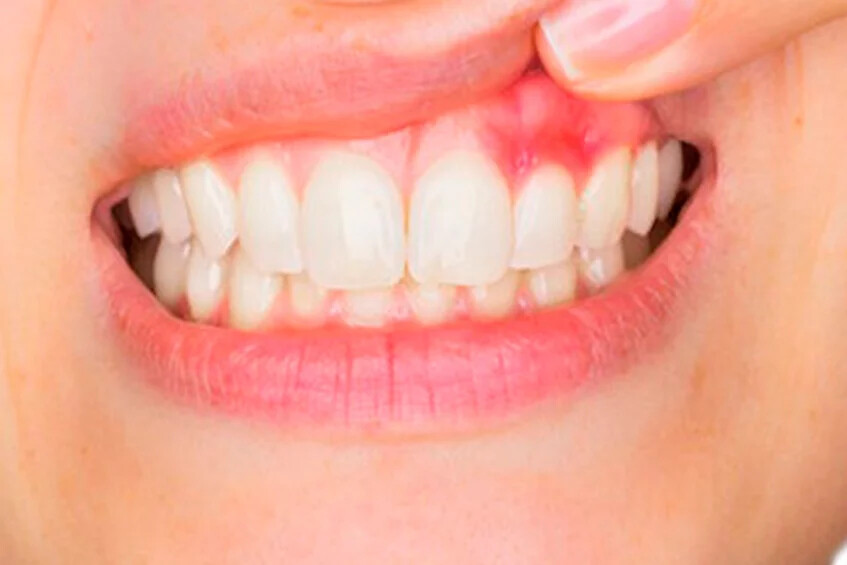

Red, sore, and bleeding gums are signs of gingivitis (the first stage of gum disease), but did you know they also can be a symptom of diabetes? If sore gums are accompanied by chronic bad breath and oral fungal infections, it may signal that something else is going on.

The high blood glucose levels that accompany diabetes allow germs to build up, and can eventually lead to tooth loss. In this case, more than one disease could be at work. When gingivitis is left untreated, it leads to periodontitis, a gum infection that creates deep pockets of germs and pus between the teeth. Treatment depends on how much to the teeth, gums, or jawbone has already sustained. Your dentist will discuss both non-surgical and surgical treatment options. You may also need blood work and medication from your family’s physician.

2. Swollen gums

While safe disease-free gums look solid and pink in color, gums that have gum disease can swell, turning red or purple in color.

5. Bleeding gums

Normally, healthy gums don’t bleed from daily tooth brushing or flossing; if your teeth bleed during your usual oral hygiene routine, you may have developed gum disease.